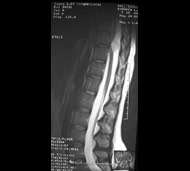

Спинальна магнітно-резонансна томографія (МРТ). Замість радіаційного випромінювання в МРТ використовуються потужні магнітні і радіохвилі для отримання зображення поперечного перерізу хребта. МРТ чітко відображає спинний мозок і нерви і забезпечує краще зображення пухлин кісток, ніж комп'ютерна томографія (КТ). Вам можуть ввести в вену кисті або передпліччя контрастну речовину, яка висвітлює деякі пухлини. Крім цього, використовують сканери з високою інтенсивністю сигналу для виявлення невеликих пухлин, які можна не помітити.